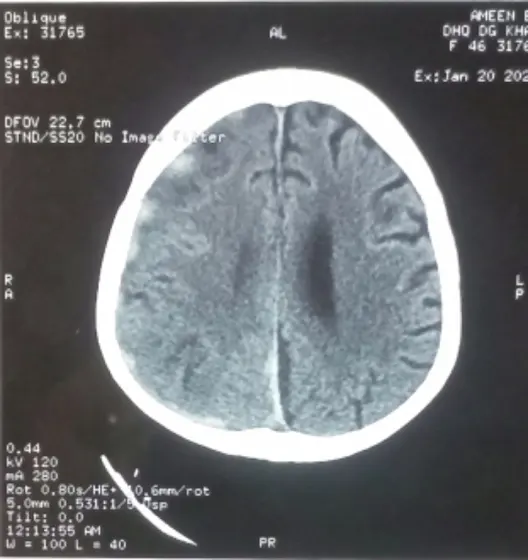

CT brain plain axial section showing hyperdense signal of haemorrhagic density along right frontoparietal convexity, suggestive of subdural hematoma. This patient was on warfarin due to mitral valve replacement. This patient presented with left sided weakness. Fortunately patient made dramatic recovery and was able to ambulate independently within one week.